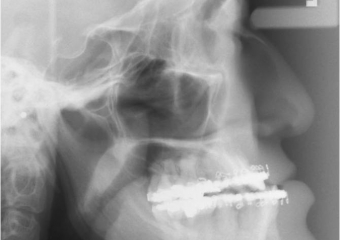

Telerradiografia após a cirurgia